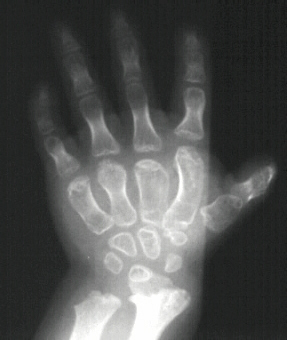

This is a two year old girl who was the product of a normal

gestation. She has two healthy half-sisters. At birth the following

problems were noted: 1. Disproportionate short-limb dwarfism with

hitch-hiker thumbs, 2. Cleft palate, 3. Bilateral clubfoot (left

worse right), 4. Respiratory difficulties because of laryngomalacia,

5. Lack of extension in elbows and knees (moderate) and 6. Cauliflower

deformity of ears occurred in the first weeks of life. She started

walking at the age of 17 months (with some flexion of hips and

knees).